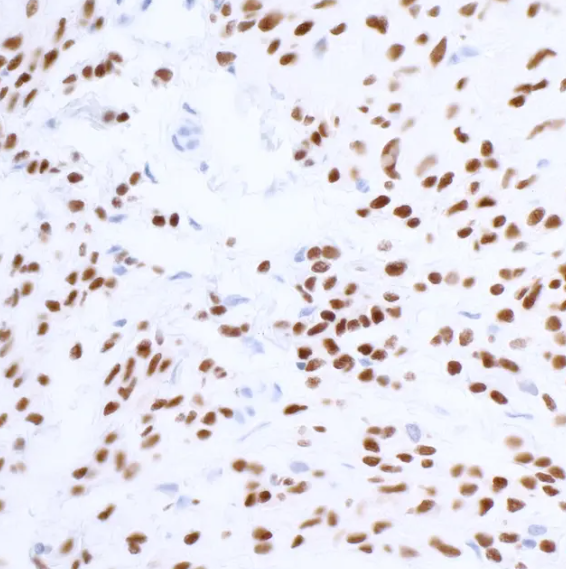

Rabbit anti-SOX10 Recombinant Monoclonal Antibody抗体

Rabbit anti-SOX10 Recombinant Monoclonal Antibody

SOX10

ICC, IF, IHC, IP, WB

应用稀释比例:(ICC) 1:100 to 1:500. Epitope retrieval with citrate buffer pH6.0 is recommended for FFPE cell sections. (IHC) 1:100 to 1:500. Epitope retrieval with citrate buffer pH6.0 is recommended for FFPE tissue sections. Immunoprecipitation (IP) 20 µl/mg lysate. Multiplex Immunofluorescence (mIF) 1:250. Western Blot (WB) 1:1000